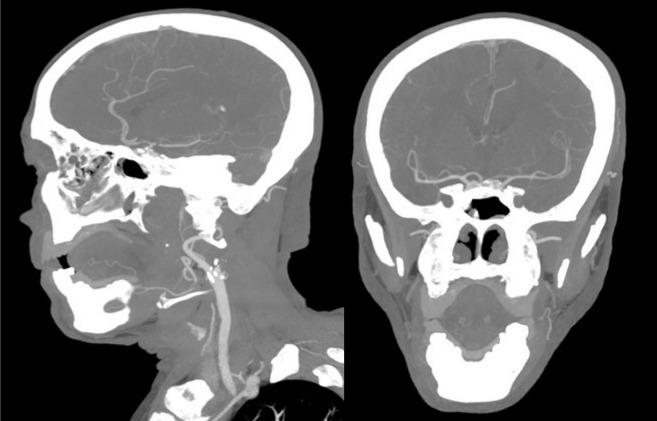

Imaging also presents diagnostic difficulties. Differentiating between extracranial and intracranial carotid occlusion can be challenging using CTA or MRA.5 Clinicians should be aware of the phenomenon of pseudo-occlusion, in which a distal intracranial ICA or proximal MCA occlusion results in absent or severely reduced antegrade flow in the cervical ICA. This may lead to non-opacification or a tapering appearance on CTA/MRA, mimicking a true proximal ICA occlusion.6,7 Furthermore, differentiating acute from chronic ICA occlusions may influence management strategies. Beyond assessing the extent of collateral circulation, specific imaging features—such as the morphology of the occlusion stump and vessel wall characteristics can aid in distinguishing acute thrombotic events from chronic atherosclerotic occlusions.8